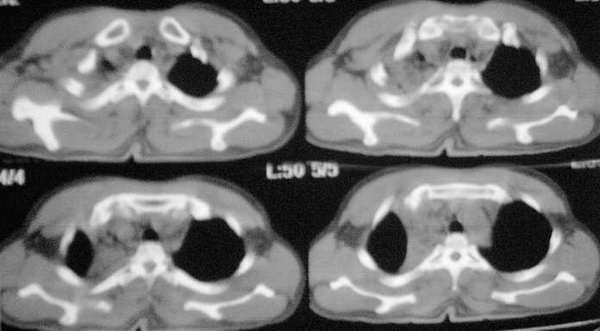

标题: CT2841:讨论.胸部外伤,是纵隔血肿还是心包积液? [打印本页]

标题: CT2841:讨论.胸部外伤,是纵隔血肿还是心包积液?

ssl1_1医生没有提供肺窗,从纵隔窗上看来似乎是右上纵隔增宽,但仔细观察发现病变边缘清楚锐利,右上叶支气管进入病灶内,病灶内可以见到残余气体密度影,所以必须要想到上叶肺不张的可能。在胸部外伤时,肺不张的发生原因是非常多而且复杂的,如支气管的断裂、管腔内血块或异物的阻塞、胸廓损伤导致呼吸肌无力、体位因素、脱水导致痰液不易咳出、胸腔积液的压迫等。心包和双侧胸腔均可见少量液体影,密度较高,应该考虑为少量积血。

该病例认为心包积液>纵隔血肿可能,其理由有以下几点:

1、该病例ct平扫见上纵隔增宽,但见向内凹弧形影,而不是向外突张力增高影,试想如果上纵隔有积血,积血量大,那么纵隔内容量增多,压力大,且纵隔线应该向外突,而该病例是向内凹的。

2、该病例楼主没有上传肺窗像,但在纵隔窗像见右上肺主支气管开口有对称性狭窄,该区隐约见“空气支气管”征。认为右上肺不张或创伤性湿肺可能。

3、主动脉弓以下大血管及心脏周围见环形低密度影,而主动脉弓以上大血管周边未见环形影。

看了12,13楼的分析受益非浅,肺窗右肺上叶不张.左下肺挫伤.